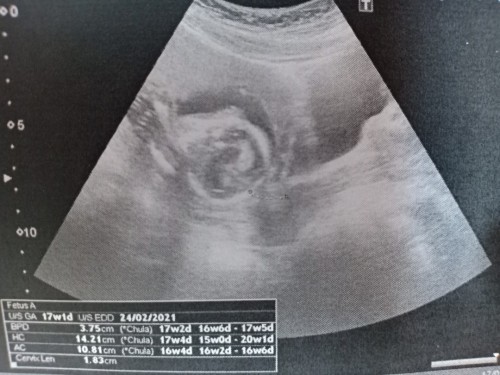

ตอนนี้เครียดมากเลยค่ะ เพิ่งไปตรวจครรภ์มาตอน 16 week 4 วัน คุณหมอแจ้งว่าปากมดลูกสั้นมาก 1.83 cm เองค่ะ(ท้องแรกไม่มีประวัติแท้งมาก่อน) มีสิทธิ์คลอดก่อนกำหนดทุกเวลา หมอจ่ายยา utrogestan 100 mg ให้กินอย่างเดียวค่ะ ใครมีประสบการณ์ปากมดลูกสั้นแบบนี้ต้องปฏิบัติตัวยังไงบ้างคะ คุณหมอแจ้งว่าถ้ามีอาการท้องแข็งถี่บ่อยๆ ให้ไปหาหมอก่อนเวลานัดได้เลยแต่เราก็ไม่รู้ว่าท้องแข็งคือแข็งแบบไหน ตอนนี้ไม่รู้ว่าเครียดหรือเพราะอะไรรู้สึกปวดหน่วงแถวหัวเหน่า ปวดท้องน้อยบ้าง ตอนนอนตะแคงก็รู้สึกเหมือนปวดท้องน้อยตุ๊บๆ ไม่รู้ว่าเป็นเพราะลูกดิ้นหรือเป็นสัญญาณบอกอะไรหรือเปล่า เวลาปัสสาวะก็จะเจ็บจิมิค่ะ